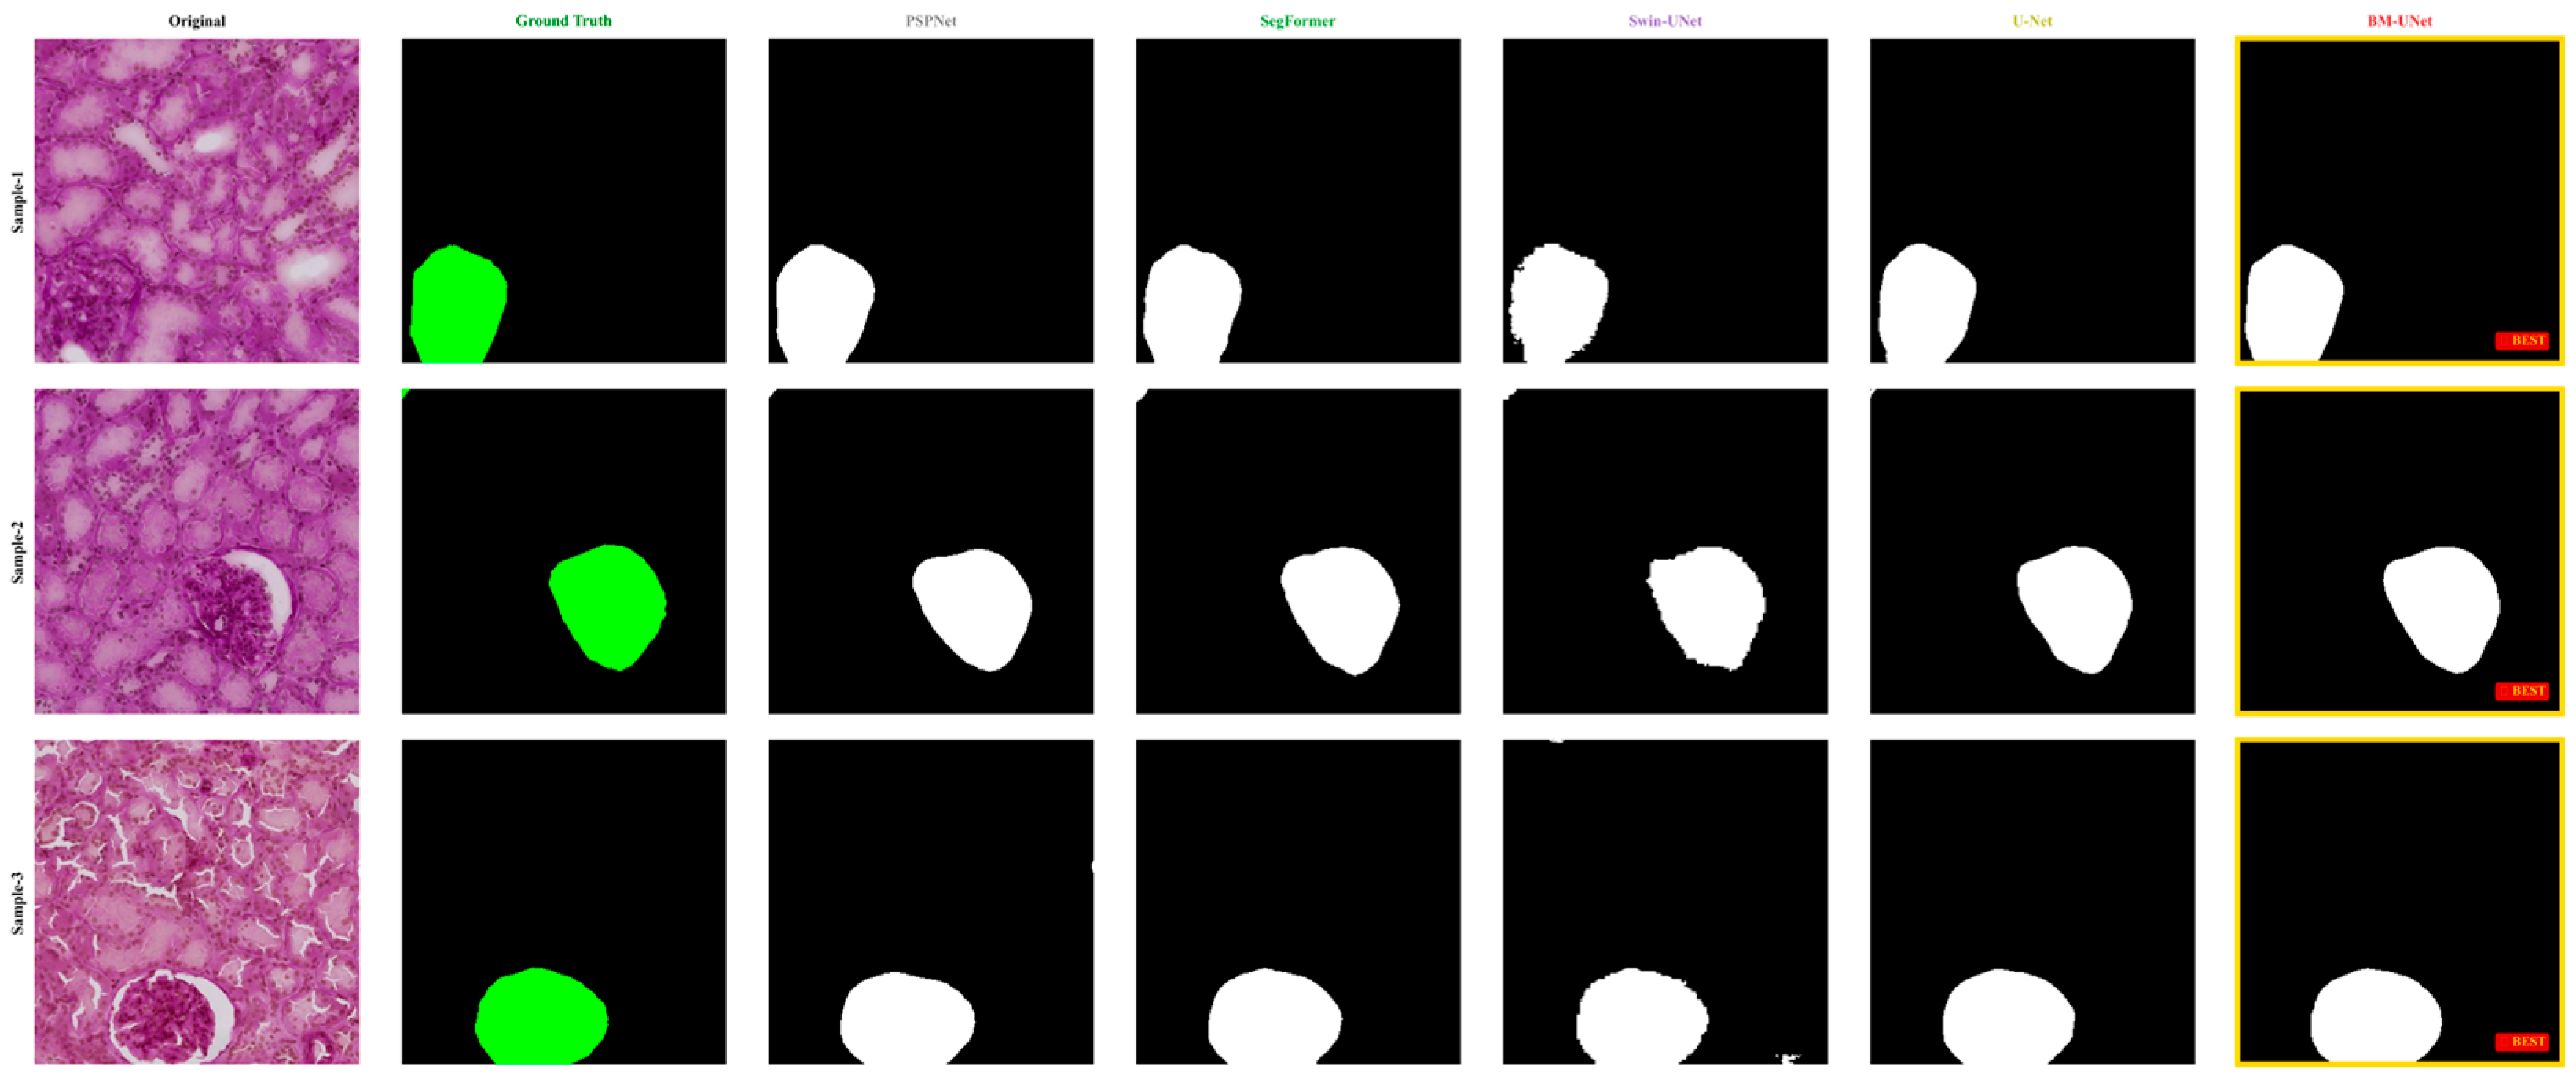

Figure 10 demonstrates BM-UNet’s superior boundary precision across diverse histopathological scenarios. Traditional CNN methods exhibit incomplete boundary capture and fragmentation, while COD-inspired approaches show improvements but struggle with completeness. BM-UNet consistently produces masks that closely adhere to actual boundary contours.

Figure 10. Qualitative segmentation comparison on KPIs2024 dataset. Columns show the original image, ground truth, and results from DeepLabV3+, Swin-UNet, SegFormer, SINetV2, BiRefNet, and BM-UNet. In the ground truth column, the glomerular regions are highlighted in green, while in all model prediction columns, the segmented glomeruli are shown in white against a black background.